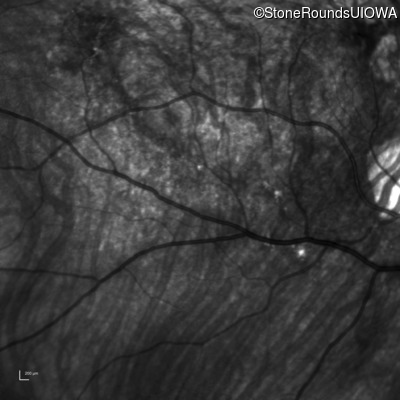

Infrared Fundus Photograph - Right - 20/20 -2 sc

Exemplar